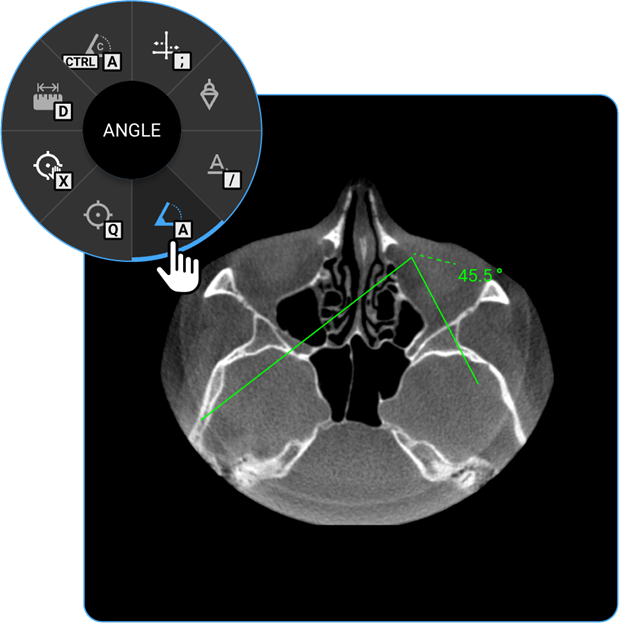

1. Angle: Click on the Angle tool to determine the angle between two intersecting lines, assisting in anatomical evaluations.

vai